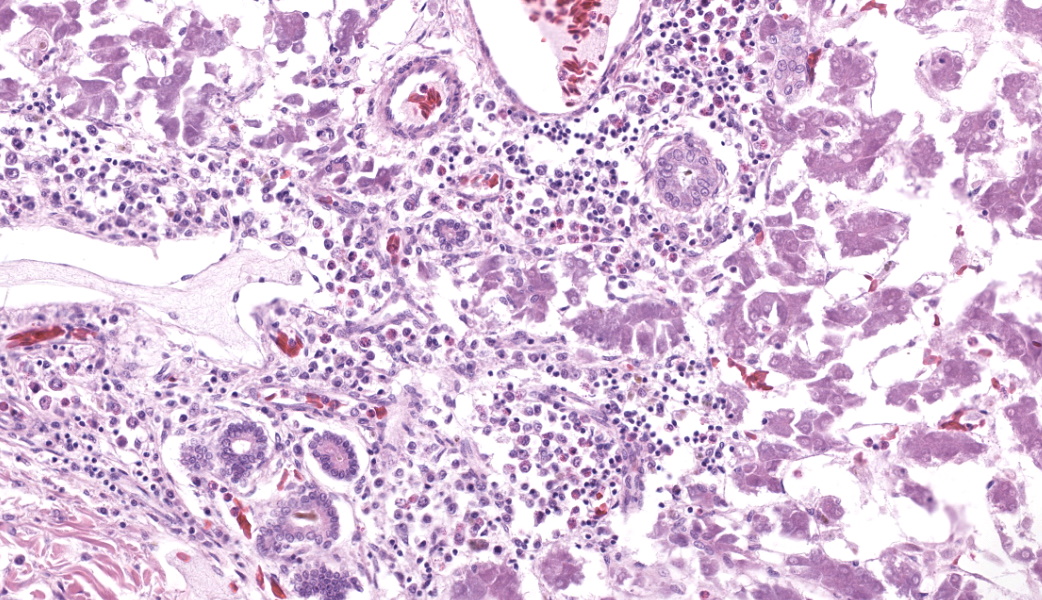

Microscopic Description:

Liver: Three sections of liver are examined. Within one section, there are multiple and coalescent, irregularly shaped granulomas replacing up to 60% of the tissue, multifocally blending in with the fibrous connective tissue of portal areas. Granulomas center around hypereosinophilic necrotic material mixed with relatively low to medium numbers of degenerate heterophils and cellular debris and multiple clusters of coccoid bacteria. Bordering the necrotic center is a layer of palisading macrophages with abundant eosinophilic and frequently vacuolated cytoplasm (epithelioid macrophages) and occasional multinucleated giant cells, which are further outlined by a robust layer of fibroblasts and collagen. Portal areas are variably expanded by medium to high numbers of lymphocytes, plasma cells, macrophages, including many laden with brown cytoplasmic granules, intermingled with numerous bile ducts (biliary hyperplasia), which extend into the adjacent parenchyma. In some portal areas, there are higher numbers of granulocytes with large, indented, vesiculate nuclei (interpreted as myeloid precursor cells and extramedullary hematopoiesis). Throughout all three sections of liver are individual necrotic hepatocytes to large regions of coagulative necrosis often centered around centrilobular veins, characterized by hepatocytes with shrunken, angular cell borders, hypereosinophilic cytoplasm and a pyknotic to karyorrhectic nucleus; larger areas of coagulative necrosis are frequently infiltrated by viable and non-viable heterophils. Within areas of necrosis and areas of viable hepatocytes are small clusters of coccoid bacteria within sinusoids.Spleen: The splenic parenchyma is interrupted by a few, relatively smaller, coalescing granulomas centered around numerous viable and non-viable heterophils, pyknotic nuclei and cellular and karyorrhectic debris, which is separated by a collar of collagen and macrophages with the occasional multinucleated giant cells. Within these regions, there are multifocal cocci bacteria colonies. There are deposits of fibrin and serum protein present throughout the sinuses and around ellipsoids. Within these foci are few reticuloendothelial cells, red cells, low numbers of lymphocytes and macrophages, as well as pyknotic nuclei and karyorrhectic and cellular debris and colonies of coccoid bacteria.

Liver: granulomatous and necrotizing hepatitis, multifocal to coalescing, severe, with intralesional cocci and biliary hyperplasiaSpleen: granulomas, multifocal, marked, with intralesional and embolic cocci

- Liver: Hepatitis, necrotizing, heterophilic and granulomatous, chronic, multifocal to coalescing, severe, with numerous cocci.

As with every case of suspected bacterial infection, a simple Gram stain can provide crucial information. Of these above-mentioned organisms, several of them are gram-negative rods, which would make them less likely with the gram-positive staining seen in this case. Mycobacterium spp, which are best revealed with acid-fast stains due to the mycolic acid in their cell wall, were not present in this case. Erysipelothrix rhusiopathiae is a gram-positive rod, but the bacteria in this case were clearly cocci. Although it can sometimes be challenging to discern bacterial morphology, participants felt confident in this case calling these cocci both on the H&E and on the gram stain. This narrowed the field substantially to Streptococcus, Staphylococcus, or Enterococcus. The contributor was able to culture Enterococcus faecalis from an aerobic bacterial culture to confirm the identity of the offending organism in this case.